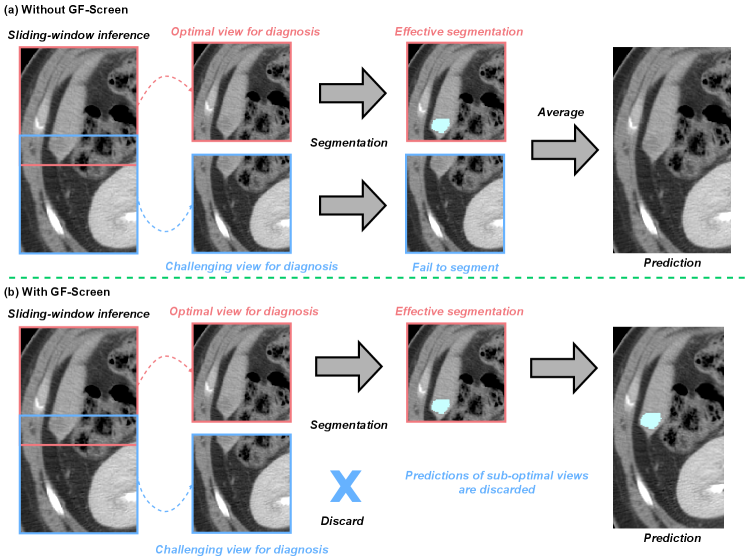

GF-Screen can improve the segmentation DSC by selecting the optimal diagnosis views, as shown in Fig. A4. The optimal view (in red) contains the complete organ and provides important information (e.g., intensity contrast) for cancer diagnosis, while the challenging view (in blue) contains partial information. Thus, the segmentation predictions of this optimal view would be more accurate. Following previous methods, we adopt sliding-window inference to crop sub-volumes with overlapped areas. However, during sliding-window inference, previous methods generally average these results, where the segmentation predictions from challenging views can degrade the average performance of the final results. Our GF-Screen can effectively select optimal views and discard the suboptimal views, mitigating their negative influence.

Refer to caption

Figure A4: An illustrative case to demonstrate the effectiveness of selecting optimal views. (a) Without GF-Screen, segmentation predictions from challenging views can degrade the average performance of the final results. (b) With GF-Screen, only the segmentation results from optimal diagnostic views are retained, while predictions from suboptimal views are filtered out.